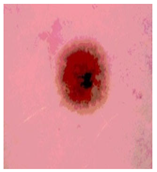

![]() | ![]() | ![]() | ![]() |

| Img1 | --- Pixel Intensity (0–255) ---> | ||

| Img2 | --- Pixel Intensity (0–255) ---> | ||

| Img3 | --- Pixel Intensity (0–255) ---> | ||

| Img4 | --- Pixel Intensity (0–255) ---> | ||

| Img5 | --- Pixel Intensity (0–255) ---> | ||

| Img6 | --- Pixel Intensity (0–255) ---> | ||

| Img7 | --- Pixel Intensity (0–255) ---> | ||

| Img8 | --- Pixel Intensity (0–255) ---> | ||

| Img9 | --- Pixel Intensity (0–255) ---> | ||

| Img10 | --- Pixel Intensity (0–255) ---> | ||